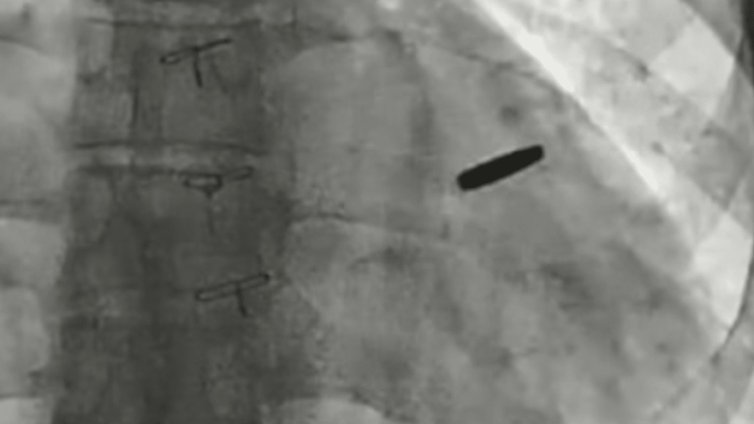

Войник, бранил "Азовстал", прекарал три години в руски плен с куршум в сърцето ВИДЕО